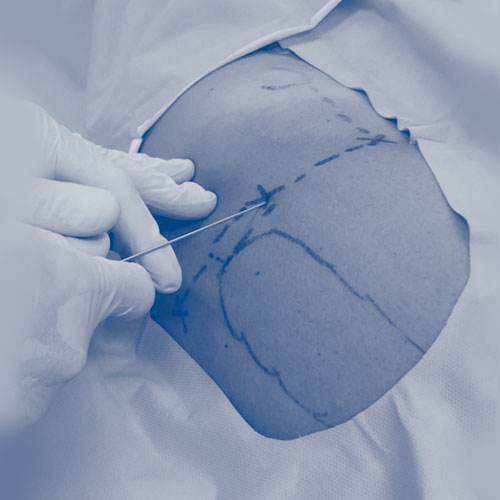

AH

cadera

Tratamientos biologicos para cadera